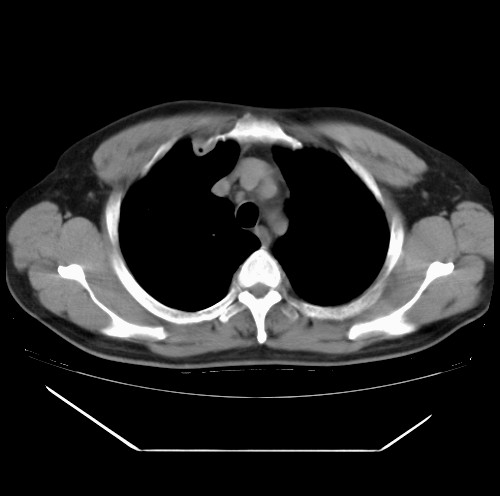

标题: CT22085:双肺多发结节

男,44岁,咳嗽,痰中带血2天。

病灶大部分位于胸膜下,结节大小相差不是很大,肺尖太干净。这种结核没见过,我认为可排除。

首先考虑转移,不除外肉芽肿、真菌感染。建议查其它。

除肺内及胸膜下可见多发大结节外,在肺小叶中心核、小叶间隔及支气管血管束上亦可见多方小结节,可以认为是随机分布。考虑转移可能性大。

仔细观察病灶形态,病灶边界部分清楚,结合临床症状,首先考虑转移,纵隔内多个肿大淋巴结影。

双肺血管纹理末端多发类圆形结节,边界光滑清晰 气管前腔静脉后淋巴结肿大

考虑转移瘤

本例双肺多发类圆形高密度灶,边清,结合病史多考虑双肺多发转移改变,可以结合实验室检查。